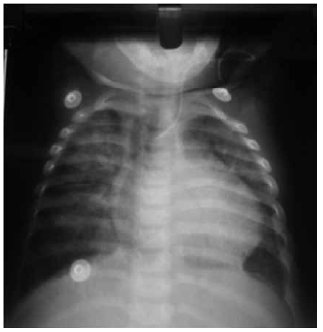

A las tres semanas de vida, tras anteriores radiografías en las que no se apreciaban imágenes patológicas a nivel pulmonar, presenta infiltrado algodonoso pulmonar bilateral que recibe tratamiento con furosemida y se piensa que se debe a la presencia de ductus permeable cardiaco. Asocia otros problemas cardiacos, a saber: foramen oval y estenosis pulmonar, diagnosticados por eco doppler. El infiltrado no mejora con este tratamiento.

Al igual que ocurrió en nuestro caso, las alteraciones en la radiografía de tórax pueden aparecer tras semanas de resultados normales, apareciendo de forma más tardía alteraciones en forma de diferentes patrones, como infiltrado bilateral, patrón neumónico, nódulos, adenopatías o patrón miliar, que es el más frecuentemente encontrado (hasta el 50% de los casos)(5). Las formas cavitadas son excepcionales(11). En muchas ocasiones los hallazgos conducen a la sospecha de otras patologías lo cual retrasa el diagnóstico, como en nuestro caso, en el cual tras la aparición de infiltrado algodonoso bilateral se pensó en una causa cardiaca, dados los diagnósticos de ductus permeable cardiaco, foramen oval y estenosis pulmonar que presenta el paciente y se administró tratamiento con furosemida.